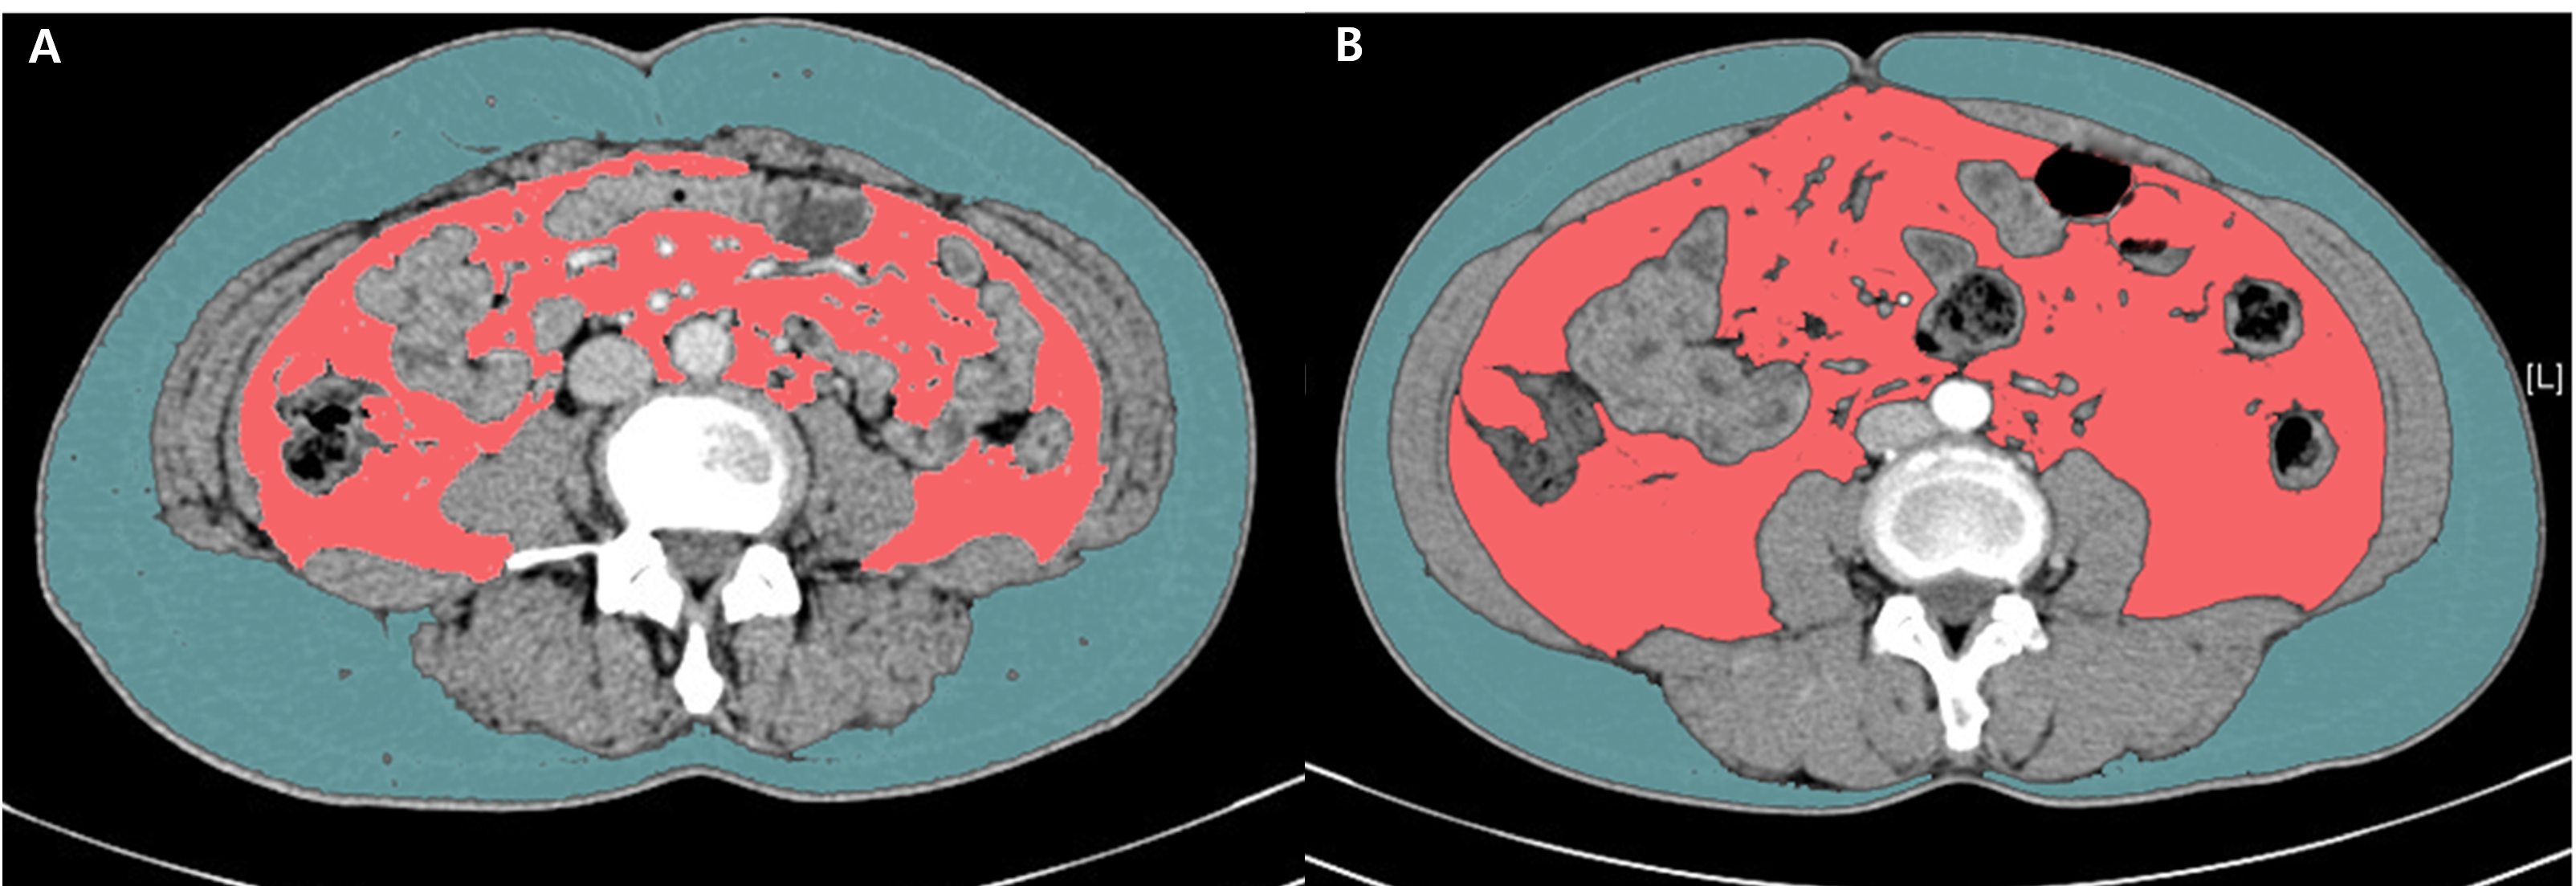

▶ 내장 지방 CT의 예. 파란색은 피하 지방, 분홍색은 내장 지방이다. A, B의 BMI는 24.7로 같지만 내장 지방 면적은 다르다. B는 핑크색 내장 지방이 많은 마른 비만 형태이다.

(출처: Shuang Ye et al. The effect of visceral obesity on clinicopathological features in patients with endometrial cancer: a retrospective analysis of 200 Chinese patients. BMC Cancer 2016; 16:209)

이 내장 지방을 CT로 평가 할 수 있습니다. CT를 통해 같은 BMI를 가지고 있지만 내장 지방 면적은 상당한 차이를 보이는 경우를 볼 수 있습니다(그림). 이 내장 지방 CT는 일반적인 복부 CT와 달리 스캔 범위는 좁으며, 주로 배꼽 부위나 요추 디스크를 기준으로 측정합니다. 촬영 이후 자동화된 프로그램을 통해 내장 지방과 피하 지방의 면적을 구할 수 있습니다. 현재까지 절대적인 기준치는 없지만, 내장 지방 면적이 100cm2를 넘거나, 내장 지방 면적/피하 지방 면적 비(V/S ratio)가 0.4를 넘는 경우 내장 지방이 많다고 봅니다.